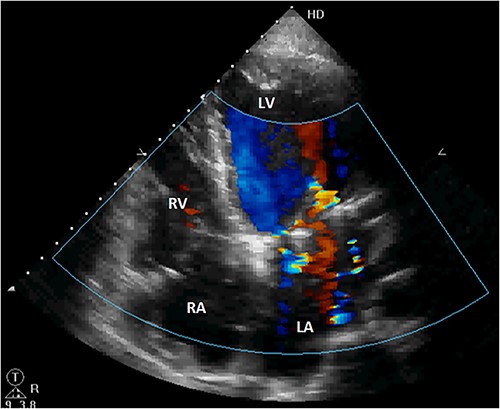

Initial physical examination showed stable vital signs. Auscultation found systolic murmurs of mitral and tricuspid regurgitations. There were no peripheral edema or other signs of heart failure. Abdominal examination revealed no tenderness, hepatomegaly or ascites. Electrocardiogram at admission showed sinus rhythm with no conduction abnormalities or signs of ischemia. Chest radiograph found an enlargement of the cardiac silhouette. Routine blood tests were normal. Transthoracic echocardiography (TTE) found a bi-atrial cystic structure, which we initially suspected to be a hydatid cyst as cystic echinococcosis is highly endemic in Morocco. Color Doppler showed a massive shunt with blood coming into the right atrium (RA) from an unknown source (Fig. 1). Cardiac magnetic resonance imaging (CMR) showed a bilobed cystic lesion hypointense on T1 and T2 sequences, with the same signal as cardiac chambers, located below and behind the left atrium (LA). The superior lobe was 48-mm wide and the inferior lobe 65-mm wide. On the peripheral wall of this structure, a giant circumflex artery (LCX), with a right atrial shunt, was present (Fig. 2). Coronary angiography (CA) along with computed tomography angiography (CCTA) confirmed the bilobed circumflex saccular aneurysm and CAF (Figs 3 and 4).

Initial TTE. (A) Parasternal short-axis view showing a bi-atrial cystic lesion; (B) apical 4-chamber view showing color Doppler aliasing in the RA, indicating a shunt. RV, right ventricle; LV, left ventricle; C, cystic lesion.

The patient was discharged after an uneventful postoperative course. The control TTE performed 2 weeks after the intervention showed that the right atrial shunt was gone (Fig. 6).

Postoperative TTE showing the disappearance of the right atrial shunt. RV, right ventricle; LV, left ventricle.